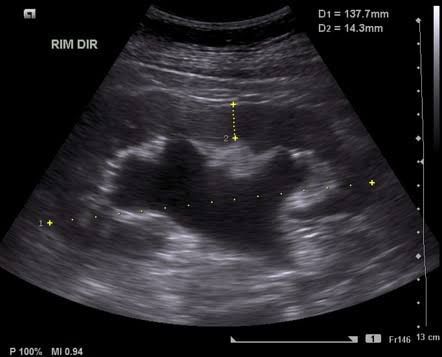

Typically, urine passes from the kidney through a tube called a ureter that drains into the bladder, and then out of the body. But, sometimes urine backs up or remains inside the kidney or in the ureter. That's when hydronephrosis can develop. Some common causes of hydronephrosis include: Partial blockage in the urinary tract. Urinary tract blockages often form where the kidney meets the ureter. Less commonly, blockages may occur where the ureter meets the bladder. Vesicoureteral reflux. Vesicoureteral reflux happens when urine flows backward through the ureter from the bladder up into the kidney. Typically, urine flows only one way in the ureter. Urine flowing the wrong way makes it difficult for the kidney to empty properly and causes the kidney to swell.